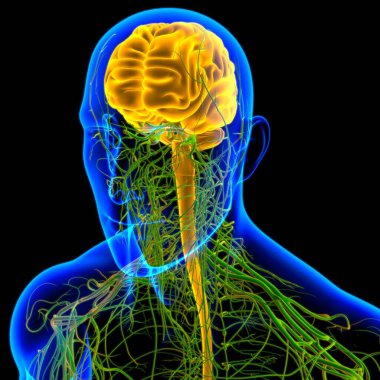

Tıbbi Konsept için sinir sistemi anatomisi olan 3D İnsan Beyni

MaviGrafikselresimlemeŞeffafİnsanSağlıkBaşıİlaçerkekkordonüç boyutlubiyolojikHücregövdeHastalıkİstihbaratİçeridebiyolojiBilimSistemAcıorgzihinomurgaelektronİşaretgörüntü oluşturmaanatomiomurilikbeyinMerkezGerginNörolojimikroskobikBeyin fırtınasıSıhhiyeanatomikSinirbeyincikcerebra3d oluşturmaüzerine siyahsinir hücresiBenzer İçerikler